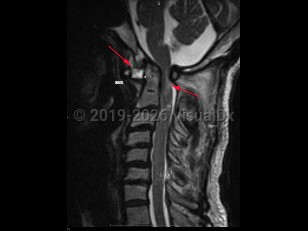

Atlantoaxial instability

Atlantoaxial instability (AAI) is defined as excessive motion between the first cervical vertebra, the atlas, and the second cervical vertebra, the axis. The atlantoaxial segment is an anatomically complex section of the spinal column, composed of unique bones, articulations, and ligaments, with critical neurovascular structures intimately involved. The atlantoaxial segment is responsible for significant motion in the spine, and, in fact, is responsible for over half the possible axial rotation of the cervical spine. Disruptions of any of the ligaments or articular processes that afford nonpathologic motion of the atlantoaxial segment may result in instability of the complex. AAI can occur due to trauma, rheumatoid arthritis, congenital abnormalities (including up to 20% of Down syndrome patients), degenerative changes, head and neck infections, neoplasms, or iatrogenic etiologies. Most commonly, AAI results from compromise of the ligamentous complex; however, fractures or destructive processes affecting the osseous elements may also result in AAI.

AAI can occur in 3 directions: rotation, flexion-extension, and distraction leading to excessive displacement, which can result in subluxation or even dislocation.

Anterior atlantoaxial subluxations are more common in adults and result from any of the pathologies listed above. Anterior subluxations result in neurologic deficits or death in one-third of patients. Patients with rheumatoid arthritis (RA) are at most risk for dislocation in the anteroposterior (AP) plane but can develop rotational AAI as well.

Posterior atlantoaxial subluxations are rare and often occur from erosion of the odontoid process of the axis.